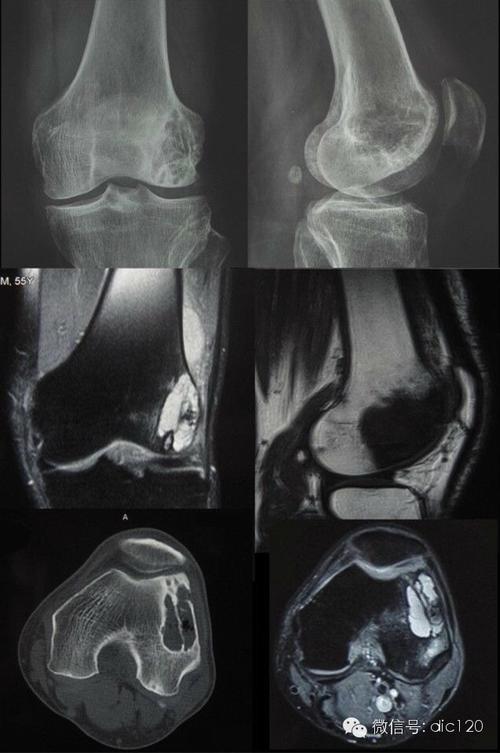

骨囊肿影像,股骨骨囊肿

髌骨骨囊肿

骨内腱鞘囊肿(邻关节骨囊肿)

动脉瘤样骨囊肿影像学解析

专题骨肿瘤样病变1骨囊肿从病理到影像

动脉瘤样骨囊肿